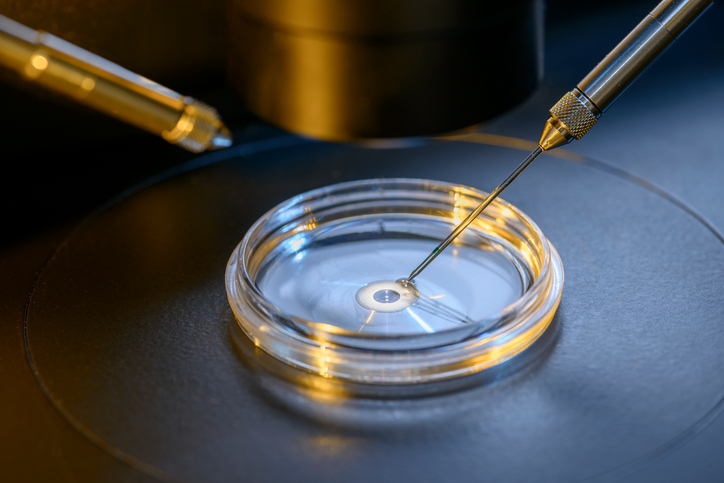

Por mucho tiempo, la pareja de Atlanta intentó tener un hijo de forma natural antes de progresar rápidamente en la Fecundación in Vitro (FIV). No obstante, sus posibilidades de quedar embarazada disminuyeron conforme pasaba el tiempo y tuvieron que recurrir a otros medios para poder concebir.

Luego de cinco intentos fallidos de FIV y un embarazo químico, conocieron la adopción de embriones, donde se implanta un embrión congelado de una pareja exitosa.

A pesar de tener una tasa de éxito del 50%, Nancy se quedó embarazada al instante y después de investigar más sobre el procedimiento, se sorprendió al descubrir que la suya había estado congelada desde febrero del año 2004.